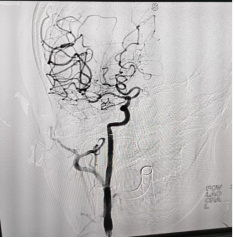

术前脑血管显影 术后脑血管显影

危急时刻,市人民医院立即开通“卒中中心”急性病救治绿色通道。启动开辟生命通道的多学科协作(MDT)机制,神经内科、神经外科、影像科等多学科专家紧急会诊。卒中医疗团队考虑到患者发病时间处于“黄金 6 小时”救治窗口内,在征得家属同意后,迅速制定了急性脑卒中急诊介入取栓治疗方案。随后,神经外科主任王晓明、神经内科副主任杜海兵、神经内科主治医师刘鑫华,麻醉科主治医师艾青慧、导管室护士长杨利等多学科医护人员同步响应紧急到位,在导管室通过微创介入方式直达血栓部位,成功抓取并取出堵塞血管的血栓,快速精准清除,重建脑部血供。整个手术历时仅50分钟,全程微创、出血少,术后造影显示,原本闭塞的大脑中动脉完全恢复血流,患者意识迅速清晰,肢体功能明显改善,言语功能也逐步恢复,手术效果立竿见影。